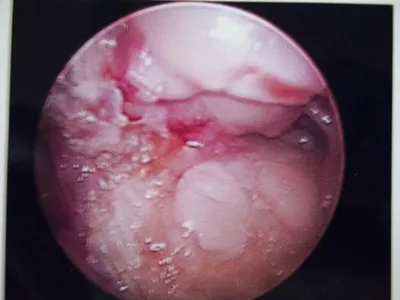

Intraop pics of synptomatic sesamoid that was completely removed.